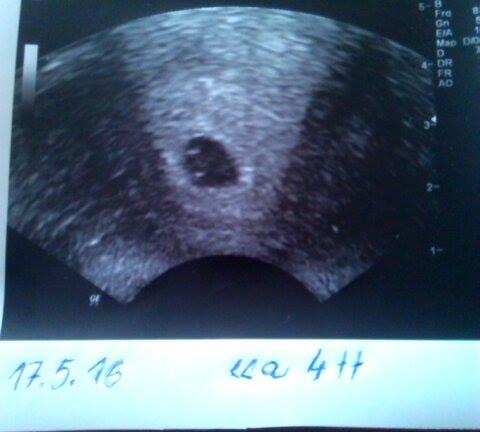

17.5 - potvrzeno těhotenství (měla jsem být podle poslední MS 6 týden, ale mimi je 4 týden)